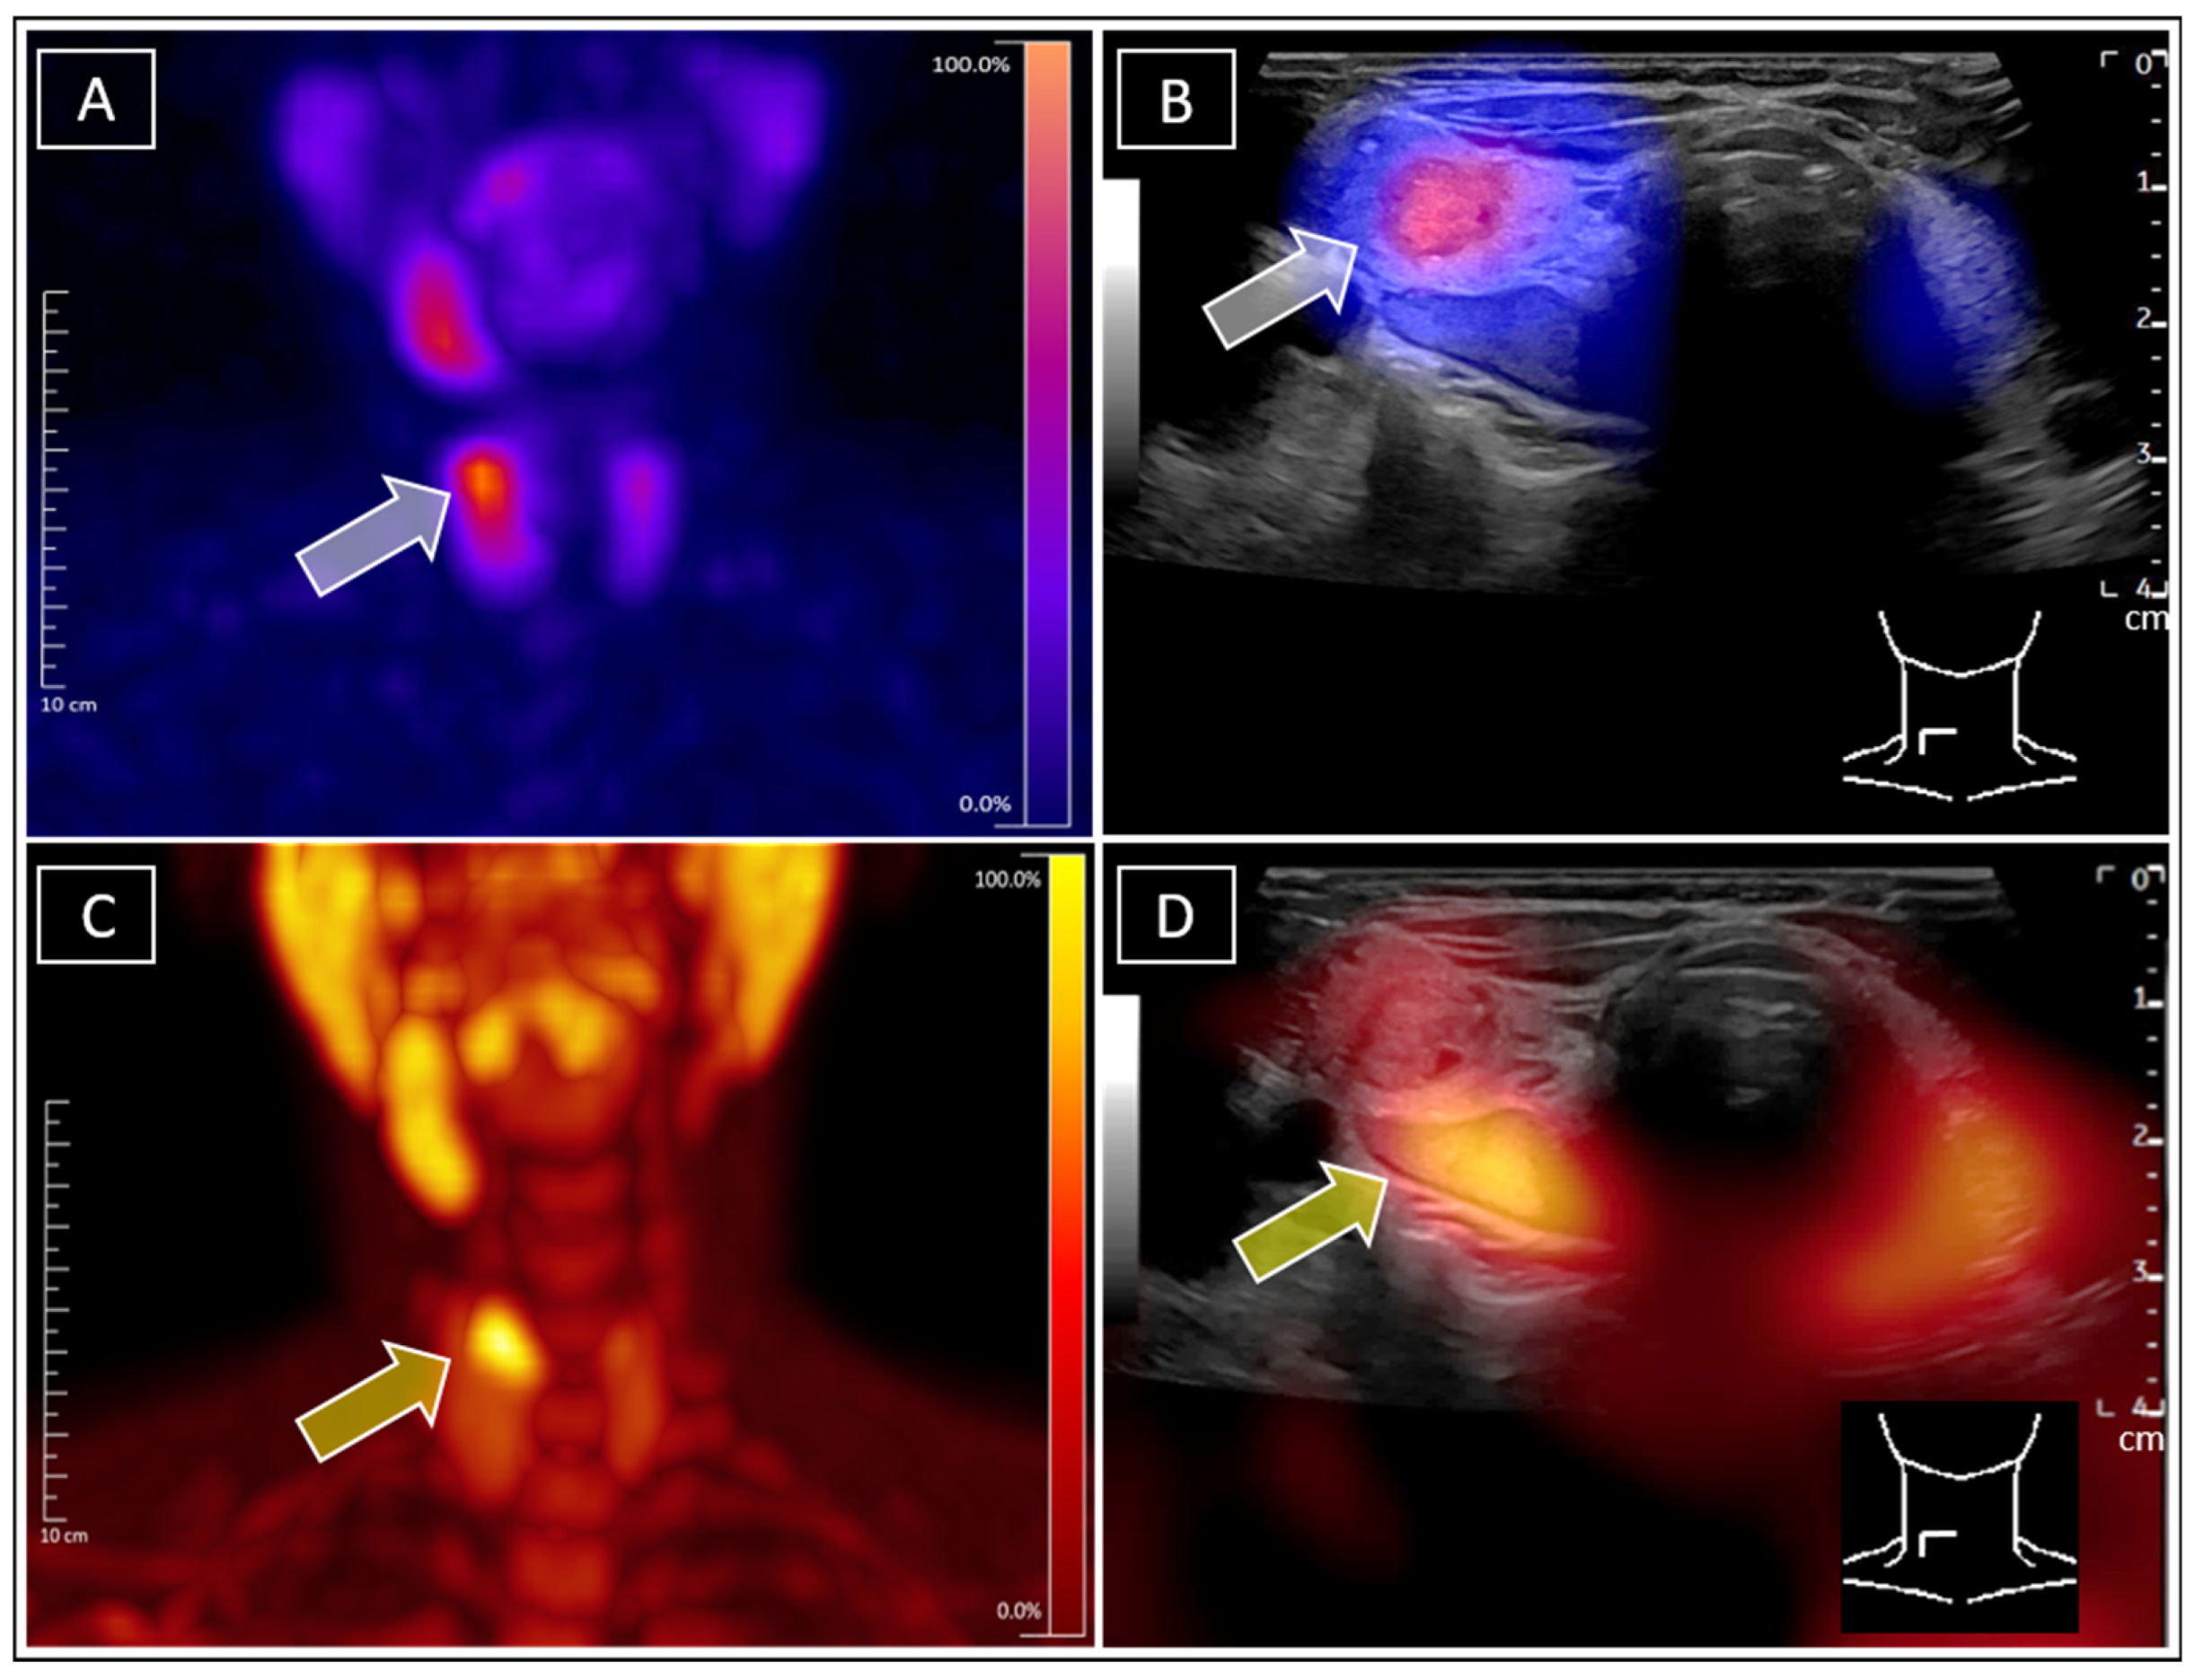

Simultaneous Identification of Tc-99m-Sestamibi-Positive Autonomous Thyroid Adenoma and Adjacent F-18-Ethylcholine-Positive Parathyroid Adenoma in Patient with Graves’ Disease Using Real-Time Ultrasound Fusion Imaging

Leder, T.; Seifert, P.; Gühne, F.; Freesmeyer, M. Simultaneous Identification of Tc-99m-Sestamibi-Positive Autonomous Thyroid Adenoma and Adjacent F-18-Ethylcholine-Positive Parathyroid Adenoma in Patient with Graves’ Disease Using Real-Time Ultrasound Fusion Imaging. Diagnostics 2025, 15, 1262. https://doi.org/10.3390/diagnostics15101262